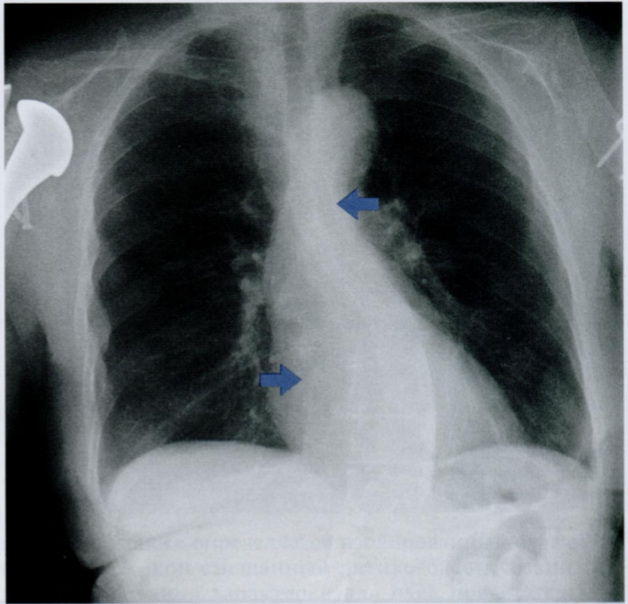

Назовите Rx признаки пневмомедиастинума

Что отмечено стрелками на снимке?

Признаки пневмомедиастинума:

1) эмфизема мягких тканей шеи

2) заметное просветление по контуру сердца или аорты, ограниченное снаружи париетальной плеврой (это то, что видно на данном снимке)

3) субкардиальное или ретрокардиальное скопление воздуха, четкая визуализация диафрагмы на всем протяжении

4) вилочковая железа у детей обнаруживается в виде «треугольного паруса» (у новорожденных - это норма)

5) пневмоторакс

6) пневмоперикард

7) воздух, окружающий ствол легочной артерии (в виде круга в боковой проекции)

На снимках воздух вдоль контуров сердца + воздух между волокон грудных мышц